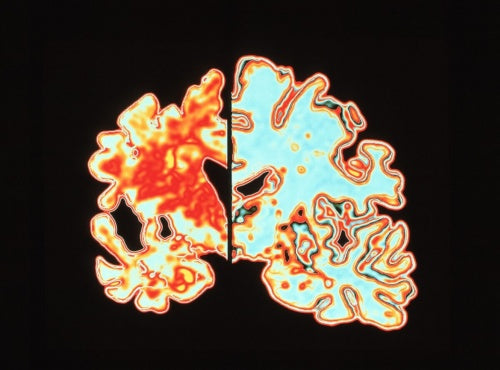

アルツハイマー病は認知症の一般的な原因だ。このCGは、アルツハイマー病患者の脳(左)と正常な脳(右)の断面を比較したもので、アルツハイマー病患者の脳が激しく萎縮しているのがわかる。(Photograph by Alfred Pasieka, Science Photo Library)